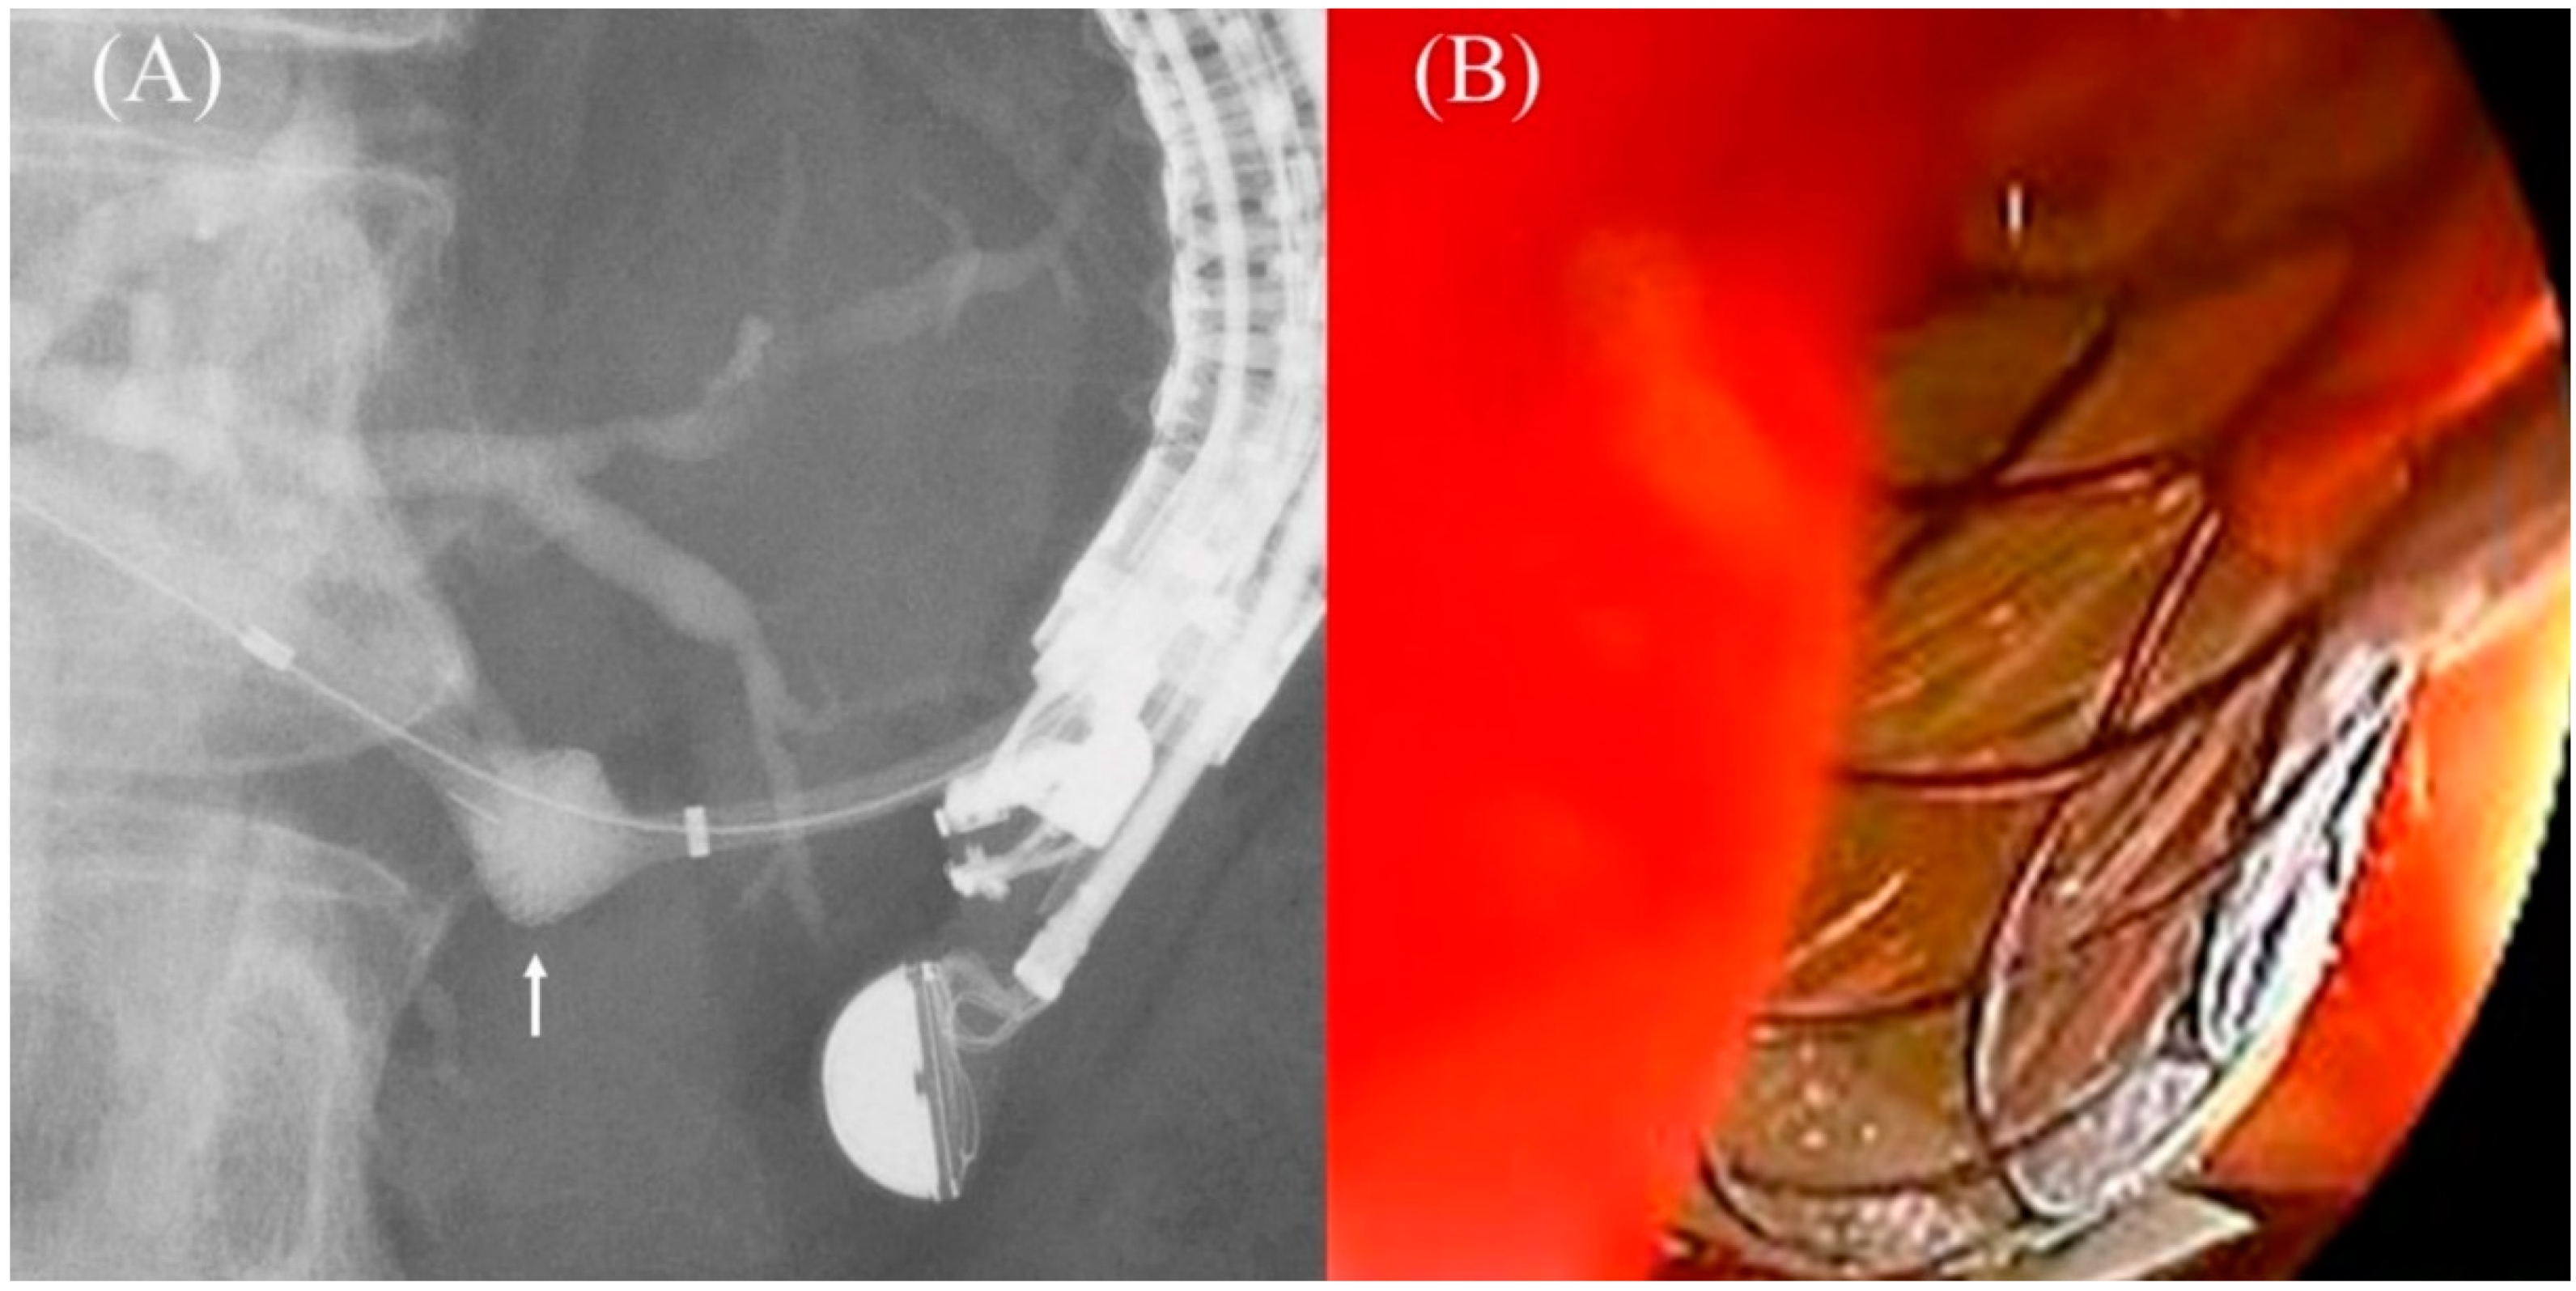

The process of partially covered SEMS deployment is as follows. First, proper positioning of the stent introducer is performed. When the introducer is inserted into the bile duct, the scope is pushed back by the counteraction and the distance between the liver and stomach is increased. Stent deployment must not be started at this point, as the stent end may fall into the abdominal cavity. The introducer should be inserted deeply once and then pulled to adjust its position so that only the uncovered portion enters the bile duct. This pulling motion will shorten the distance between the liver and stomach. The next step is to detach the SEMS from the introducer. After positioning the introducer, the assistant pulls on the outer sheath to gradually release the SEMS. At this time, the introducer is retracted into the scope channel due to the counteraction, and the stent is advanced. The physician must pull the introducer as the assistant works, while watching the fluoroscopic view to ensure that the tip position of the stent remains the same. Once the uncovered area is fully expanded, the stent is fixed to the liver, and the physician’s pulling force draws the liver into the scope, bringing the liver and stomach even closer together. The last step is SEMS implantation, which requires the scope to be pulled away from the gastric wall in order to bring the SEMS out of the channel. If the scope is simply pulled back, the pushing force of the scope will be lost, and the gastric wall will be moved away from the liver. As a result, the stent length in the abdominal cavity becomes longer while the stent length in the stomach becomes shorter, and the end of the stent may migrate into the abdominal cavity. To avoid this problem, “Intra-channel (conduit) release method [86,87]” is essential. The physician pulls the introducer as the assistant moves to deploy the stent but stops the deployment once the fluoroscopy shows that the tip of the outer sheath has been pulled about 1 to 2 cm inside the channel. At this point, the physician pushes the introducer in the opposite direction, and the expanded portion of the stent emerging from the channel is pressed strongly against the gastric wall (Figure 21A). This action creates a gap between the scope and the gastric wall, and stent deployment across the gastric wall can be directly confirmed (Figure 21B). Afterwards, the assistant resumes pulling the outer sheath, and the released stent pushes the gastric wall forward, and the counteraction pushes the scope back. By gradually loosening the push of the introducer and the up angle of the scope while feeling the counteraction force, the scope can be released from the gastric wall while keeping the stomach and liver close together, and finally the stent is completely released in the stomach. The trick of this method is to push the expanded part of the stent, which has been partially released in the channel, against the gastric wall; pushing without intra-channel release will only cause the introducer to enter the fistula.

Figure 21.

Intra-channel (conduit) release method. After pulling the introducer until 1 to 2 cm release inside the channel, push the expanded part of the stent (arrow) to strongly press the gastric wall for keeping the stomach and liver close together (A). Stent deployment across the gastric wall can be directly confirmed by endoscopic view (B).